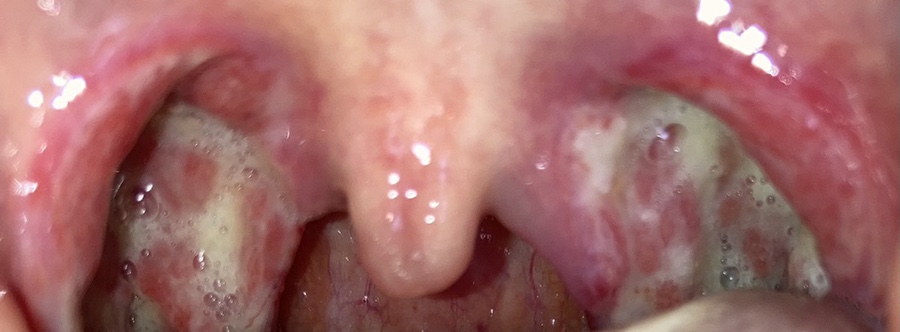

이거 수술 후 사진 찍은 거

목이 너무 부어보이지 않는 호도야 혀뒤에 있다; 잠도 제대로 못자고 옆으로 누워야 한다. 누워서 자면 숨을 못쉬게 된다ㅋㅋㅋ 1층 내려가서 의사를 만나 목도 보고 출혈 등 주의사항을 말해 주고 병실에서는 약도 가루약으로 엄청 많이 받아서 12시쯤 퇴원했다.

목이 말랐지만 전기로 지진이 있었다고 하는데 3일째에 딱지가 많이 생겼다. 사진은 3일째와 4일째가 같기 때문에 4일째는 찍지 않았다.

5일째 되니 딱지가 나왔다. 목젖도 아직 부은 것 같아. 그리고 목이 너무 아픈… 아직 옆에 자야 돼 그리고 목이 너무 부어서 그런지 내가 잘 때 “이” ~~~~~~~하는 소리가 났다고 한다. 인터넷으로 찾아보니 수면장애였다. 목이 이렇게 부었는데 안 살릴 수가 없지.

점점 살이 보인다. 그러나 역시 통증은 사라지지 않는다.

11일째 새벽에 굉장히 목에 뭐가 들어가는 느낌이었는데 딱 봐도 딱지가 떨어진 느낌이라 꿀꺽꿀꺽 삼켰다. 맛 완전?아침에 일어나서 목 보니깐

너무 벗겨졌네! 그 후로는 사진을 찍지 않았는데 왜냐하면 며칠 동안 계속 이런 상태였다. 딱지가 떨어졌는데 하품은 하면 아파서 죽는다. 꾹 참아야 한다.